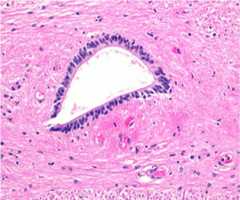

Columnar ependymal cells

Columnar ependymal cells lining the central canal of the spinal cord

Image: “Histological image (H&E) of the human central canal” by Erfanul Saker, Brandon M Henry, Krzysztof A Tomaszewski, Marios Loukas, Joe Iwanaga, Rod J Oskouian, and R. Shane Tubbs. License:CC BY 3.0